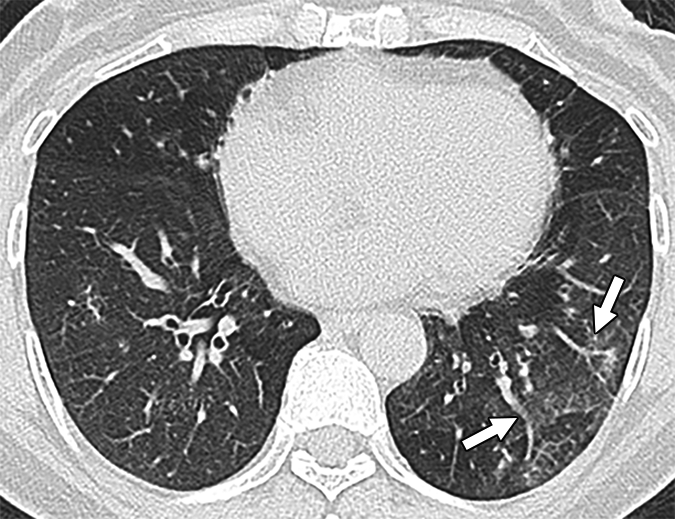

Research reveals lung findings not typically associated with viral pneumonia.

The modality is an effective, reliable alternative to chest CT or chest X-ray in this vulnerable population.

Adhering to a policy of using lung ultrasound as an initial scan reduced the use of other imaging options.